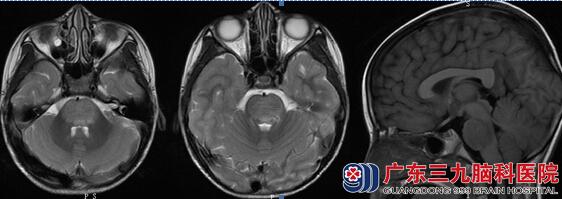

入院查体:意识清楚,不能言语,查体欠配合。定向力、判断力、自知力、记忆力、计算力检查不合作。双侧肢体肌力3级,肌张力低,腱反射减退。我院头部磁共振提示:脑桥肿胀,示团片状长T1长T2异常信号,FLAIR序列呈高信号,左侧顶叶示斑片状长T1长T2异常信号,FLAIR序列呈高信号。DWI检查脑干病变呈稍高信号,ADC图呈稍高信号,其ADC值为(0.973±0.081)×10-3mm2/s。(图一) 诊断考虑为:脑干病变性质待定:脱髓鞘?肿瘤?由于小林脑干病变性质不明,不排除肿瘤,进一步行头颅MRS检查,结果提示:单体素MRS检查:NAA/Cr比值约为1.28,Cho/Cr比值约为1.30。取右侧额叶正常脑质为感兴趣区,NAA/Cr比值约为1.83,Cho/Cr比值约为1.19。(图二)经过影像科专家会诊,考虑为脱髓鞘性质可能性大。给予激素冲击治疗,患者症状迅速好转,约10天后恢复进食、讲话清晰,行走有力,半月后痊愈出院。

图一